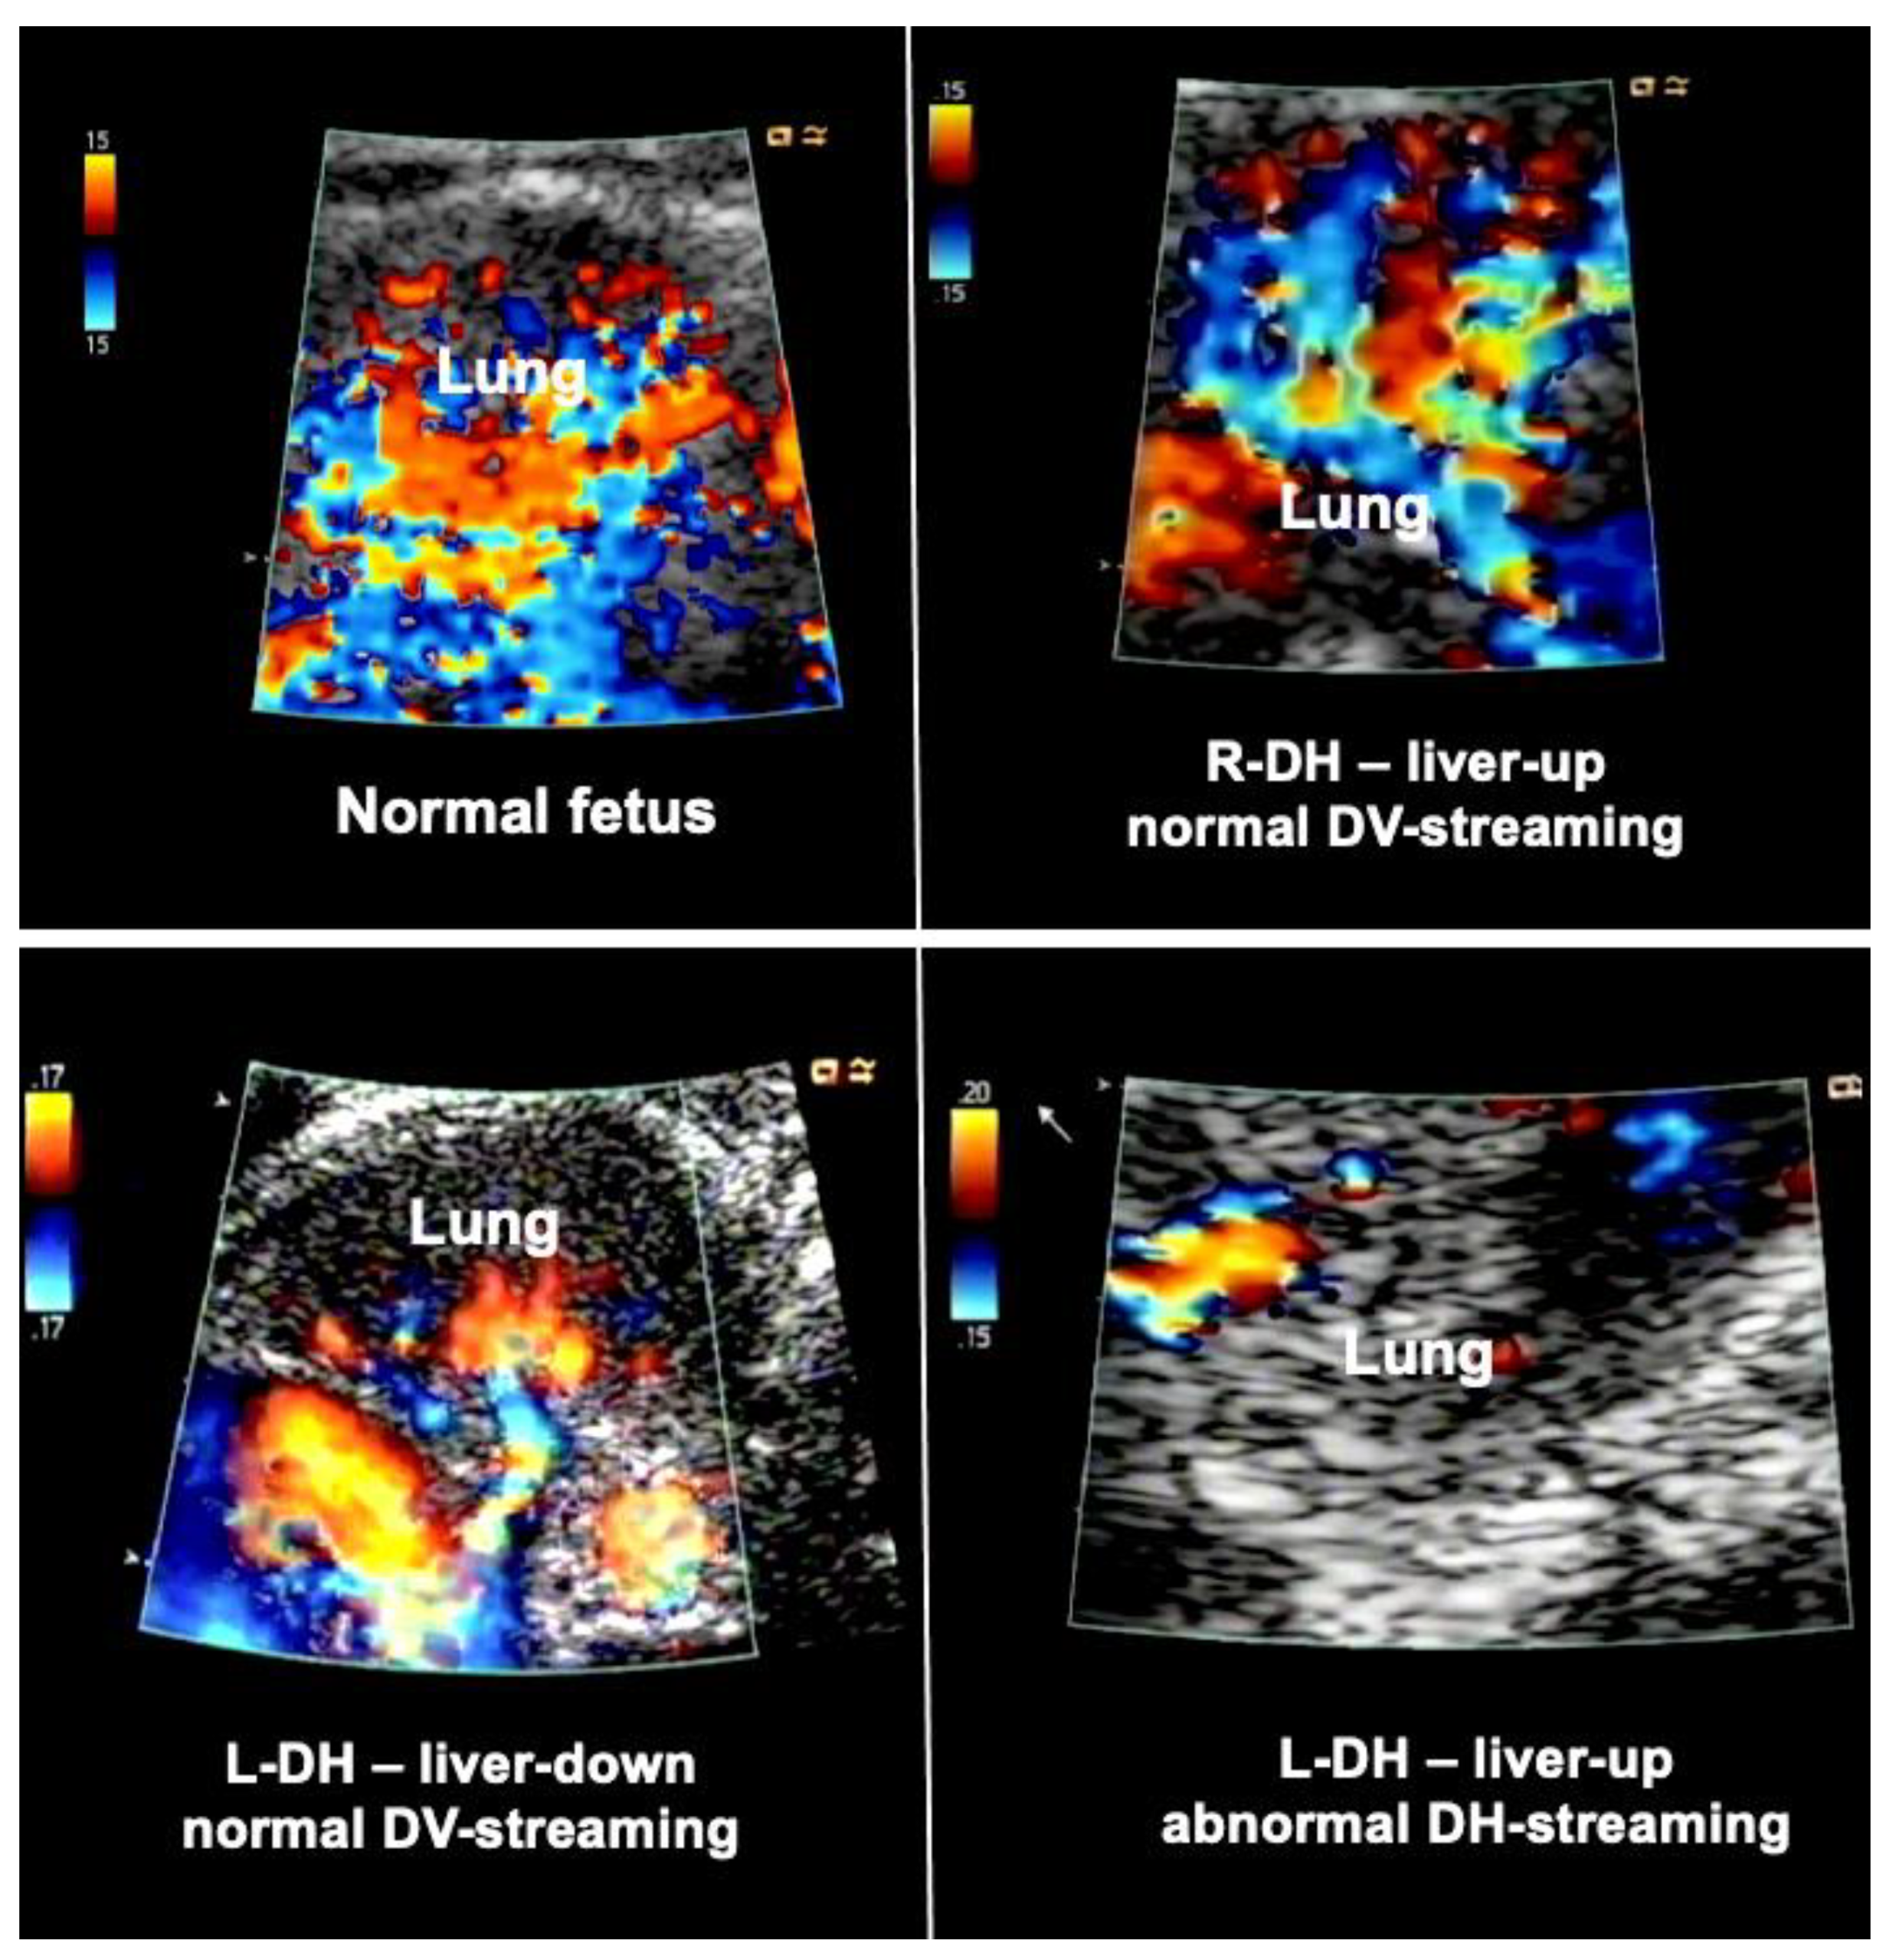

Figure 3.

Examples of lung blood flows of a normal fetus (top left) and fetuses with diaphragmatic hernia during diagnostic materno–fetal hyperoxygenation. Most fetuses with liver-down left diaphragmatic hernia (L-DH) exhibit normal streaming of ductus venosus blood into the left side of the heart (bottom left). As a result, both sides of the heart are of equal size, pulmonary blood flow signals are easily visualized, and pulmonary vasodilation in response to diagnostic maternal hyperoxygenation can be produced. In contrast, most fetuses with liver-up L-DH exhibit preferential streaming of ductus venosus blood into the right side of the heart of the fetus. As a result, there is less preload to the left side of the heart, which in turn becomes hypoplastic. In addition, pulmonary blood flow is often markedly decreased (bottom right). Fetuses with right diaphragmatic hernia (R-DH), despite liver herniation, present with normal ductus venosus streaming into the heart. Therefore, as a rule, in these fetuses, neither isolated left, nor isolated right heart hypoplasia are observed, and color Doppler signals of pulmonary blood flow are often normal (top right).

In contrast, most fetuses with liver-up left diaphragmatic hernia exhibit preferential streaming of ductus venosus blood into the right side of the heart of the fetus. As a result, there is less preload to the left side of the heart, which in turn becomes hypoplastic. Probably as a result of the oxygen-enriched ductus venous blood reaching the lungs, morphologic changes contributing to pulmonary hypertension can develop. During Doppler ultrasound studies, pulmonary blood flow signals are less pronounced and pulmonary vasodilation in response to materno–fetal hyperoxygenation is often markedly attenuated (Figure 3).

In contrast, fetuses with right diaphragmatic hernia—despite liver herniation—present with a more normal infracardiac spatial arrangement of venous vessels, and hence, normal distribution of ductus venosus blood within the fetal heart [43]. Therefore, as a rule, in these fetuses, neither isolated left, nor isolated right heart hypoplasia are observed (I have encountered only one exception) (Figure 3). Nevertheless, there may be symmetrical underdevelopment of both, left and right cardiovascular structures, from compression by the herniated organs. Yet even in severe cases, a close to normal degree of blood flow can be observed within the left lung (Figure 3). In ECMO centers such as ours, this hemodynamic advantage seems to contribute to survival rates of more than 80% for this condition [34].